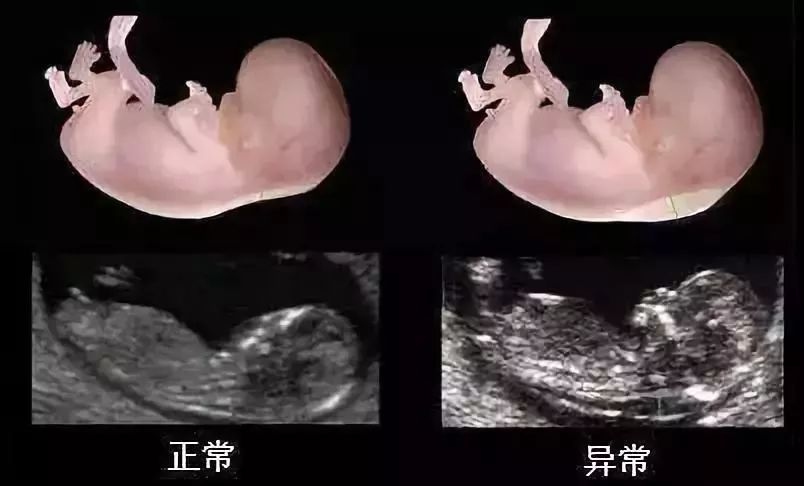

NT检查,那些不得不说的事

孕早期胎儿健康第一关的NT检查,你知道这些“小秘密”吗?

NT检查:孕妈咪一定要懂的第一次胎儿排畸!_搜狐健康_搜狐网

做NT检查必要性